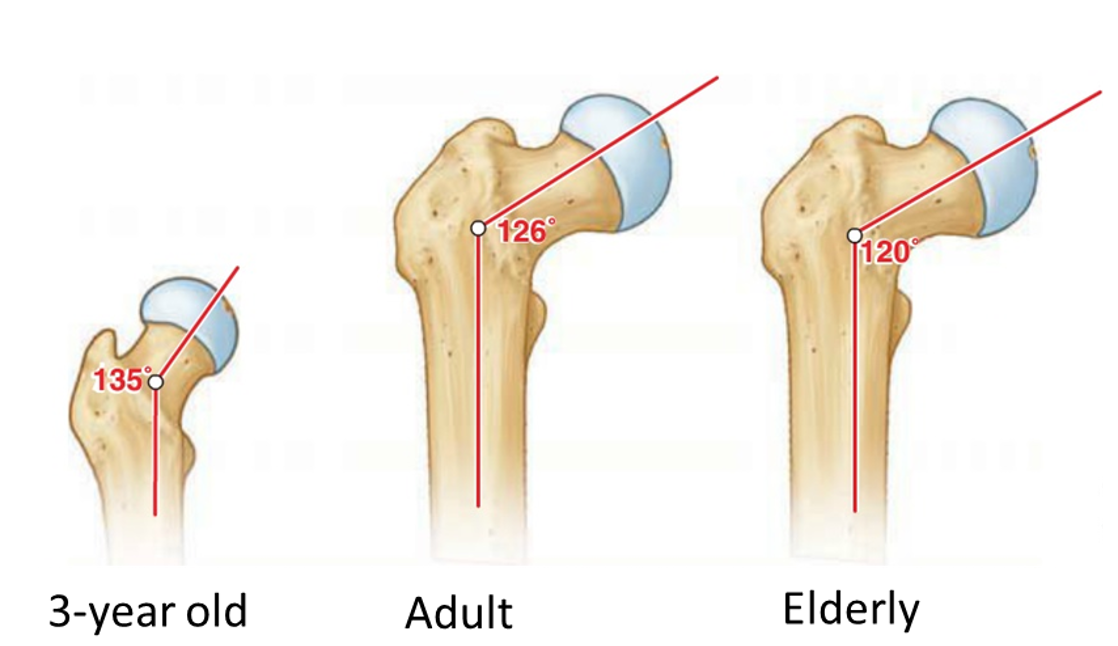

Angle of Inclination: angle between the

femoral neck and femoral shaft

angle of inclination is greatest at what time in life?

birth

as you get older what happens to the angle of inclination?

it decrease

*The decreasing angle of inclination with age puts greater stress on the neck of the femur

which can result in fractures (femoral neck) in patients with osteoporosis